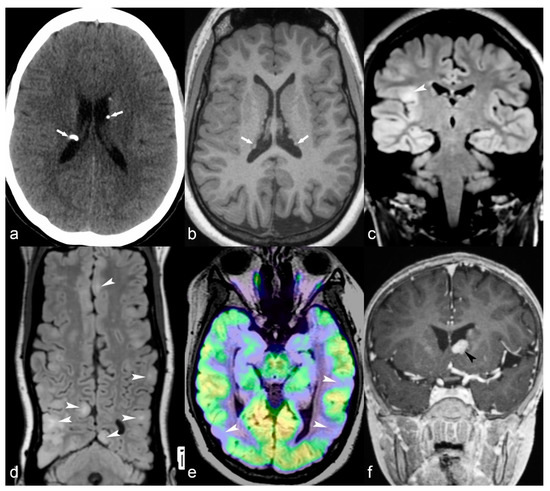

Figure 4.

36-year-old woman. The right hippocampus is smaller than the left (arrows) as seen on coronal T2WI (a), FLAIR (b) and MP2RAGE (c) and shows hyperintensity on T2WI and FLAIR. There is also flattening and loss of the normal undulations of the right hippocampus, suggestive of hippocampal sclerosis.